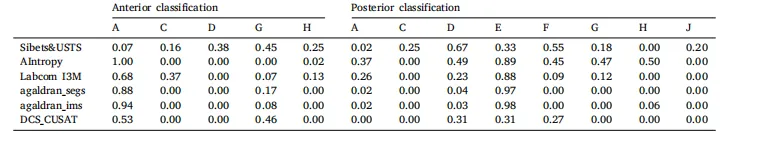

Table 4Recall per class for anterior and posterior classification.

表 4 前部和后部分类中每个类别的召回率